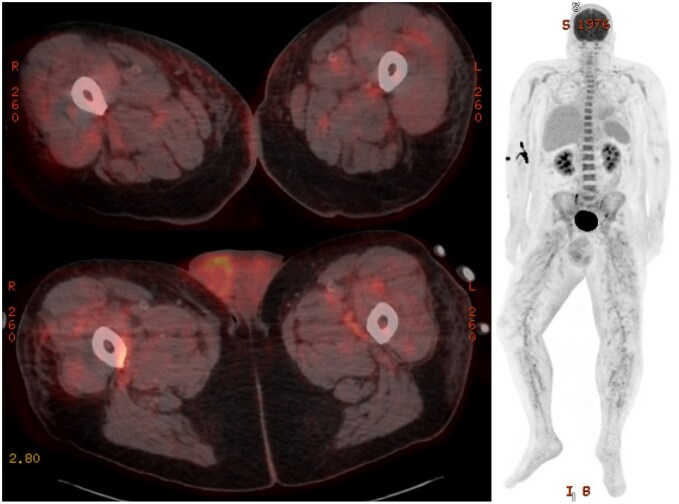

结节性多动脉炎(PAN)是一种全身性中小血管炎。它通常与乙型肝炎感染有关,典型表现为皮肤、胃肠道或神经系统受累。我们提出了一个病例56岁的男性谁提出了一个主诉的痛苦阴囊肿胀。最初的超声检查显示有附睾炎,患者开始使用适当的抗生素,但症状没有改善,因此入院。由于持续的阴囊疼痛、发烧和阴性的感染检查,F-18氟脱氧葡萄糖(FDG) PET/CT显示弥漫的高代谢活动贯穿中至小动脉血管,涉及血管炎。盆腔血管造影证实了诊断,患者开始使用类固醇并计划使用环磷酰胺。临床睾丸受累是一种罕见的PAN表现,尽管它经常在尸检中看到。以前报告的病例除了体质症状外,还表现出类似的阴囊疼痛和压痛,并使用类固醇和免疫抑制剂治疗。虽然组织病理学活检或血管造影通常是诊断PAN的金标准,但本病例也证明了F-18 FDG PET/CT在核医学诊断中的应用。结节性多动脉炎在F-18 FDG PET/CT上典型表现为中小血管的高代谢活动,最常见于下肢。由于类似的发现,本病例有助于报道核成像在诊断血管增生中的应用。

Polyarteritis nodosa (PAN) is a systemic small to medium vessel vasculitis. It is often associated with hepatitis B infection and classically presents with cutaneous, gastrointestinal, or nervous system involvement. We present a case of a 56-year-old male who presented with a chief complaint of painful scrotal swelling. Initial ultrasound demonstrated concern for epididymitis, and the patient was started on appropriate antibiotics without improvement of symptoms, resulting in admission. Due to continued scrotal pain, fevers, and negative infectious work-up, F-18 fluorodeoxyglucose (FDG) PET/CT was obtained, revealing diffuse hypermetabolic activity throughout the medium to small arterial vasculature, concerning for vasculitis. Abdominopelvic angiography confirmed the diagnosis, and the patient was started on steroids with plans to initiate cyclophosphamide. Clinical testicular involvement is a rare presentation of PAN, although it is often seen at autopsy. Previously reported cases have presented with similar scrotal pain and tenderness in addition to constitutional symptoms, as well as treatment with steroids and immunosuppressive agents. While biopsy with histopathology or angiography often serves as the gold standard for the diagnosis of PAN, this case also demonstrates the diagnostic utility of nuclear medicine with F-18 FDG PET/CT. Polyarteritis nodosa typically demonstrates hypermetabolic activity of the small- to medium-sized vasculature on F-18 FDG PET/CT, most often in the lower extremities. With similar findings, this case contributes to reports that show the utility of nuclear imaging in diagnosing vasculitides.